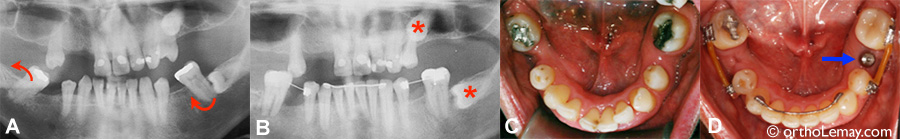

Le cas GL: les radiographies

Radiographies montrant le redressement de molaires obtenu pendant les corrections orthodontiques.

(A) Avant le traitement, deux molaires inférieures sont sévèrement basculées.

(B) Après les corrections, les molaires redressées permettront la pose d’implants pour remplacer les dents manquantes. À noter la présence de 2 dents incluses (*) que le dentiste a préféré laisser en place à cause des risques reliés à l’extraction de ces dents.

(C) Arcade inférieure avant le traitement.

(D) Après les corrections, la position redressée des molaires permet la pose d’un implant.

Caractéristiques du cas GL

Cas mutilé: malocclusion corrigée pour permettre au dentiste de remplacer les dents manquantes à l’aide d’implants dentaires.